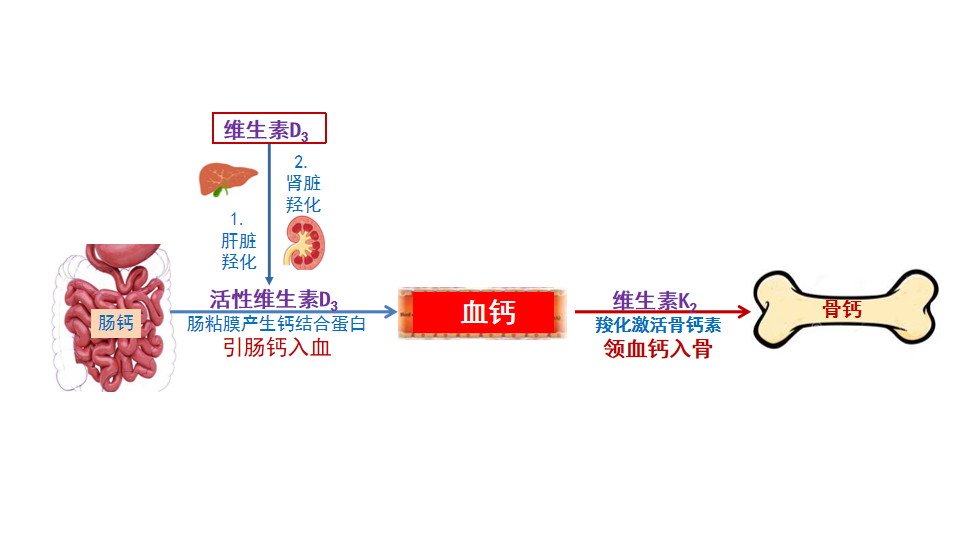

成骨细胞分泌胶原纤维,叫类骨质,柔韧而富有弹性。同时成骨细胞还分泌骨钙素入血。骨钙素的任务是把血液中的离子钙抓住,送进骨质,融入到类骨质中,这样柔韧的类骨质就变成了坚硬的骨质。初分泌入血的骨钙素是不具活性的,没有捕获钙的能力,必须将它们激活,才能行使捕获离子钙的职责。骨钙素的激活剂就是维生素K2。

(3)维生素K2激活骨钙素领钙入骨

维生素K2能激活血液中的骨钙素,撮合骨钙素与离子钙结成终生伴侣,并把离子钙领回家。骨骼才是离子钙的最后归宿,从此离子钙就结束了流浪生涯,改名骨钙,成为骨骼强大的中坚力量。

维生素K2激活骨钙素示意图